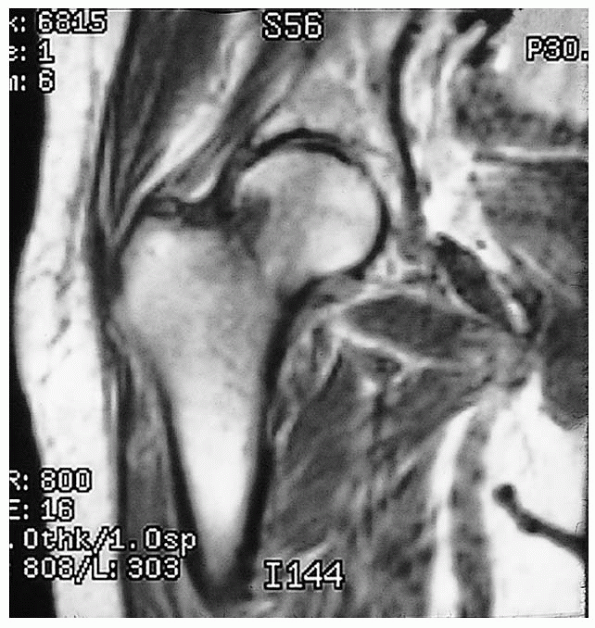

![]() |

FIGURE 21-8. Magnetic resonance image shows a nondisplaced, right femoral neck fracture.

MRI has been shown to be at least as accurate as bone scanning in

identification of occult fractures of the hip and can be performed

within 24 hours of injury. MRI within 48 hours of fracture does not,

however, appear to be useful for assessing femoral head viability or

vascularity or predicting the development of osteonecrosis or healing

complications.